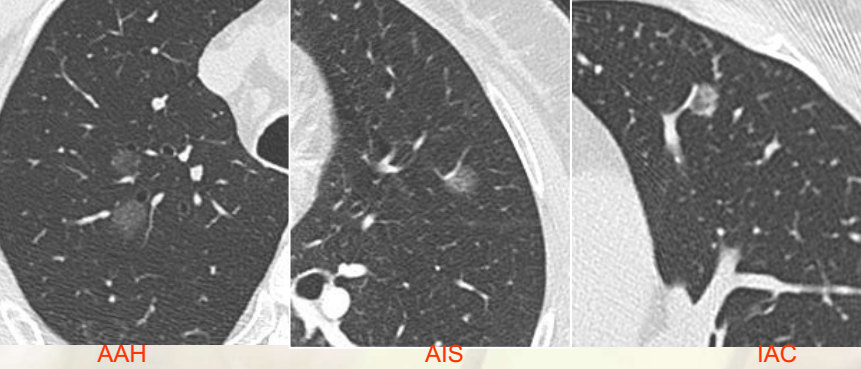

MSCT在肺腺癌亚型分型中的临床应用

861x369 - 80KB - JPEG